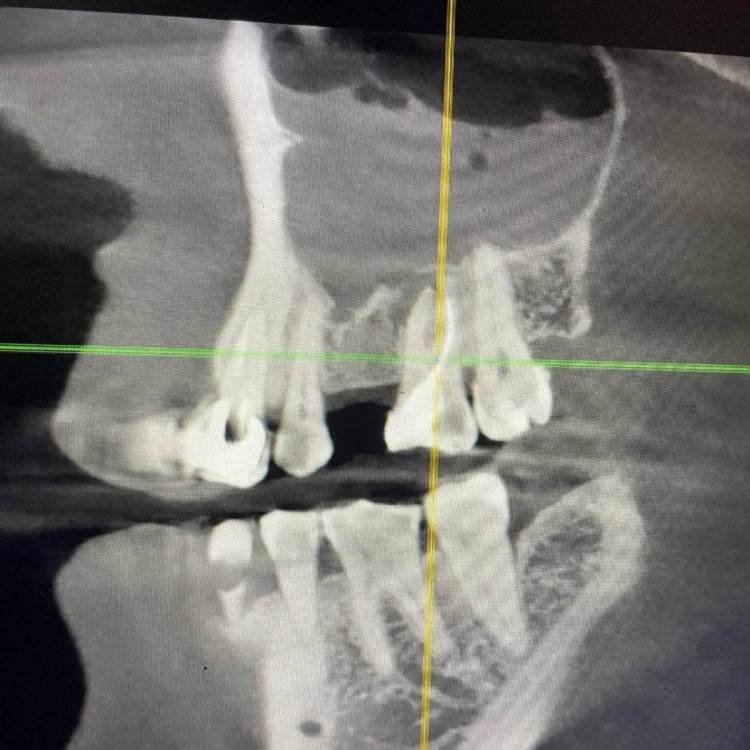

1586Doc Опубликовано 10 февраля, 2020 Автор Поделиться Опубликовано 10 февраля, 2020 (изменено) А где контроль на сегодня? При таком качестве снимков оценить будет тяжело.первые 2 фото снимки 9 месяц назад, до ревизии Изменено 10 февраля, 2020 пользователем 1586Doc Ссылка на комментарий

Паращук Роман Опубликовано 10 февраля, 2020 Поделиться Опубликовано 10 февраля, 2020 первые 2 фото снимки 9 месяц ранее до ревизии Имхо пока не вижу успеха. (( Ссылка на комментарий

1586Doc Опубликовано 10 февраля, 2020 Автор Поделиться Опубликовано 10 февраля, 2020 (изменено) Имхо пока не вижу успеха. ((ну если еще с 46 я могу понять, 45 явно деструкция в разы меньше. 100% месяца через 3-4 назначу клкт Изменено 10 февраля, 2020 пользователем 1586Doc Ссылка на комментарий